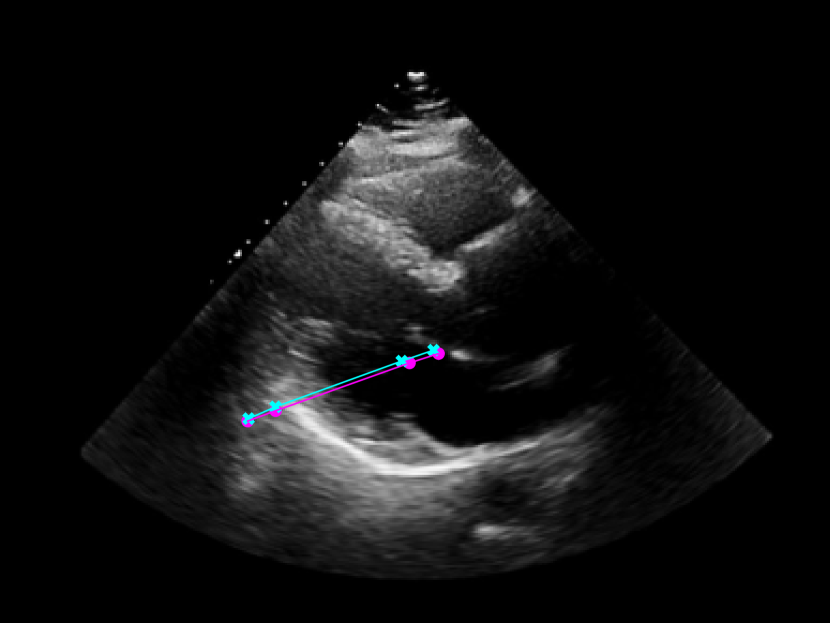

As seen in Figure 4, the model was trained to identify four key points in the echocardiogram videos: the beginning and end of the intraventricular septum (IVS), and the beginning and end of the left ventricular posterior wall (LVPW). These points were used to calculate the lengths of the IVS and LVPW, and the internal diameter of the left ventricle (LVID).